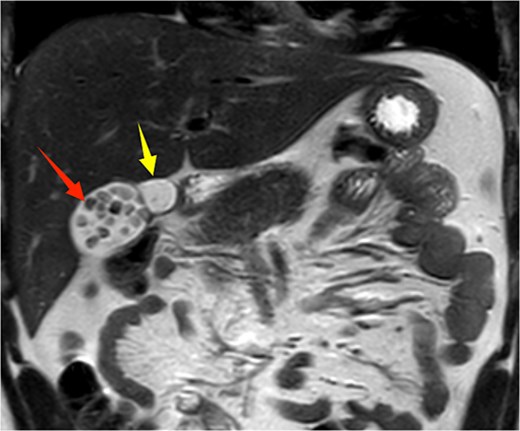

Given the patient’s recurrent biliary colic, laparoscopic cholecystectomy was decided. During surgery, adhesions between the gallbladder and the surrounding omentum were carefully dissected. After mobilizing the hepatic porta, the anatomy of Calot’s triangle was meticulously identified, confirming the double gallbladder malformation as preoperatively suspected. The two gallbladders had independent cystic ducts draining into the common hepatic duct (Fig. 3). The lateral gallbladder contained multiple stones, while the medial one was stone-free. A single cystic artery, originating from the right hepatic artery, was observed passing posteriorly between the two cystic ducts before supplying the gallbladders. The cystic ducts were sequentially clipped and transected using bioabsorbable clips. Postoperative specimen dissection revealed two gallbladders measuring 8.5 × 3.0 cm and 8.5 × 2.5 cm, respectively. The serosal surfaces of the two gallbladder bodies were adherent, and each had an independent cystic duct inserting into the common hepatic duct, confirming an "H-type" double gallbladder malformation (Fig. 4). Pathological examination reported a double gallbladder malformation: one with a slightly roughened mucosa, wall thickness of 0.2 cm, multiple stones, and features of adenomatous cholecystitis; the other with a smooth mucosa, wall thickness of 0.1 cm, and no significant stones. The patient recovered well and was discharged on the first postoperative day.

Postoperative specimen showing two completely independent gallbladders, each with its own separate cystic duct.